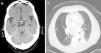

En la tomografía axial computarizada (TC) craneal se evidenció una lesión nodular de 1cm, de localización supraselar y contornos bien definidos, relacionada con la parte superior del tallo hipofisario, con moderado realce con el contraste (fig. 1a). Se planteó como primera posibilidad que estuviera en relación con el tallo hipofisario, infundíbulo o estructuras meníngeas adyacentes. La resonancia magnética (RM) encefálica mostró un nódulo supraselar de 1cm, dependiente de tallo hipofisario que afectaba al hipotálamo y al quiasma óptico, compatible con un adenoma. En la angiorresonancia del polígono de Willis no se encontraron hallazgos de interés. En la RM de hipófisis se observó una masa de 1,5 × 1 × 1,8cm que afectaba al tallo hipofisario y a la región hipotalámica, compatible con metástasis. Se practicó una gammagrafía ósea que fue normal. Al paciente le fue dada el alta en neurología y fue seguido en consultas externas. Tres meses más tarde ingresó de nuevo por febrícula y esputos hemoptoicos, motivo por el cual se consultó con neumología.

La radiografía de tórax no mostró cambios significativos respecto a la anterior y en la TC toracoabdominopélvica se apreciaba una lesión infiltrativa de densidad partes blandas que rodeaba al hilio izquierdo y se extendía a la pirámide basal, con leve disminución de volumen en lóbulo inferior izquierdo y derrame pleural bilateral (fig. 1b). La broncoscopia reveló una tumoración en el segmento sexto izquierdo, siendo la biopsia compatible con carcinoma indiferenciado de célula pequeña. La espirometría mostró trastorno obstructivo en grado severo, con prueba broncodilatadora negativa. Con el diagnóstico de metástasis hipofisaria con hipopituitarismo secundario a carcinoma indiferenciado de célula pequeña (estadio IV), el paciente inició tratamiento quimioterápico, permaneciendo estable y reduciéndose el tamaño tumoral en los primeros 6 meses, falleciendo un año más tarde por progresión de la enfermedad.